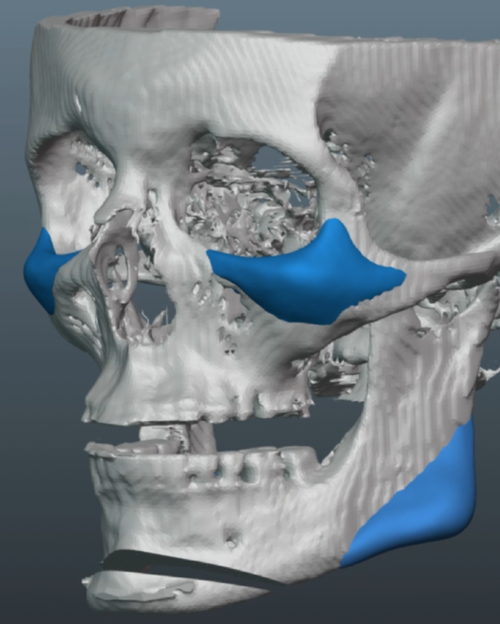

Old silicone wraparound:

Old silicone wraparound: